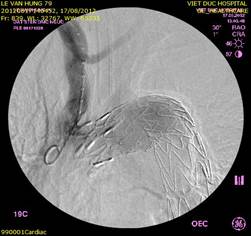

Can thiệp mạch vành qua da là một kỹ thuật dùng một loại ống thông nhỏ (catheter) để đưa một bóng nhỏ vào lòng động mạch vành bị tắc rồi nong và đặt Stent (giá đỡ) để làm tái thông dòng máu. Trái với phẫu thuật bắc cầu nối chủ...

Câu hỏi 91: Can thiệp động mạch vành là gì? Nong động mạch vành là gì? Đặt stent động mạch vành là gì? Khi nào cần làm? Làm như thế nào? Chuẩn bị ra sao?